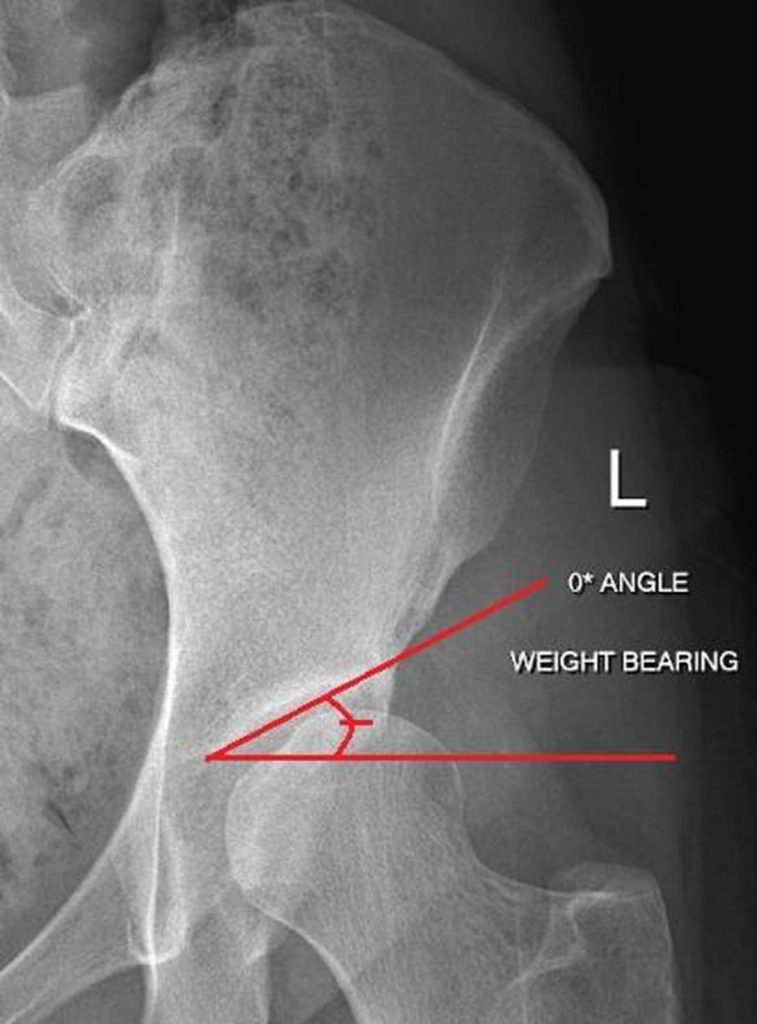

Acetabular Index / Angle of Sharp

Hips with dysplasia have increased forces along the weight-bearing parts of the hip socket. This can cause cartilage damage and early arthritis. An increased acetabular index is seen with dysplasia and results in increased forces being loaded across a smaller surface area which causes increased pressure and stress in the joint.

> 42-45 degrees = acetabular dysplasia